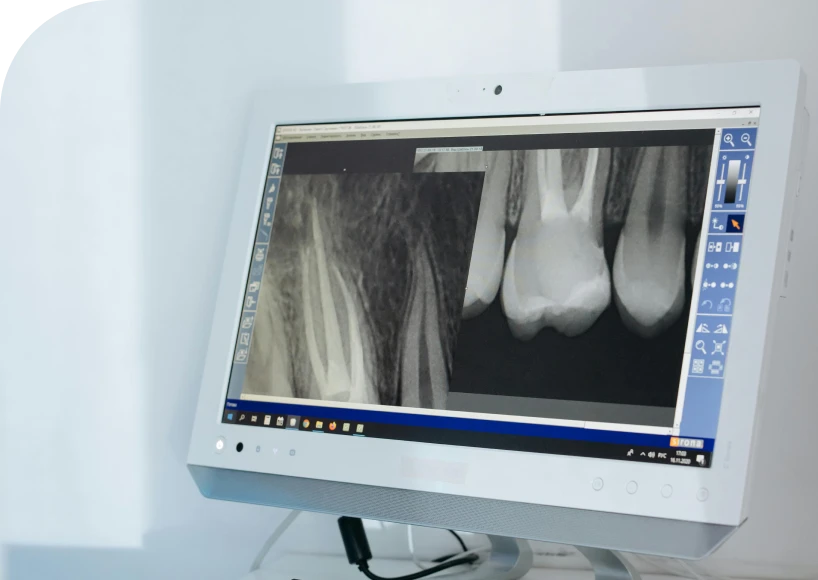

Par exemple, un canal accessoire infecté peut passer inaperçu. Une fracture radiculaire peut également se révéler longtemps après le traitement. Par conséquent, la douleur réapparaît, ou bien une image radiologique montre une lésion persistante.

Avant l’intervention, le praticien effectue un examen approfondi. Le plus souvent, il demande un cone beam, ou imagerie 3D. Cette radiographie permet de visualiser précisément la lésion et la racine concernée.